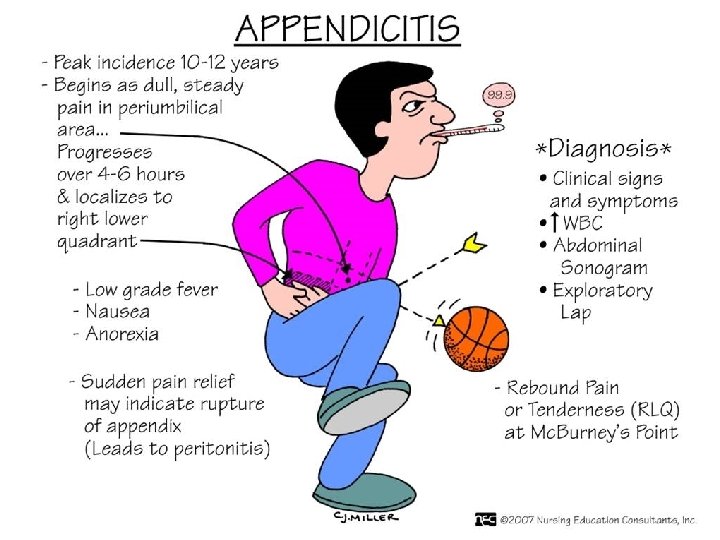

Apendisiti akut eshte inflamacioni i appendiksit, eshte nje nder shkaqet e abdomenit akut dhe gati 60% e urgjencave abdominale.

• Inflamacioni i apendiksit ndodh pas bllokimit te pjesshem/te plote te lumenit te apendiksit nga masa fekaloide, masa parazitare, trupa te huaj, tm.

• Kanali i bllokuar zgjerohet, tendoset, krijohet staze e qarkullimit te linfes, iskemi, mikroinfarkte deri ne gangrene te apendiksit. • Ketu ndodh edhe invadimi bakterial i hapesires apendikulare dhe inflamacioni I cili zhvillohet shtrese pas shtrese me hiperemi e deri ne infiltrim purulent.

KLINIKA: • DHIMBJA: Fillimisht e moderuar ne forme kolike ne regionin periumbilikal, me pas shnderrohet ne dhimbje te qendrueshme e zhvendosur ne kuadrantin inferior dexter.

NE PALPIM: - Mac Burney (+): 1/3 e poshtme e distances prej umbilikusit ne spina iliake anteriosuperior

- Rebound (+): dhimbja e madhe gjate heqjes se menjehershme te dores palpuese ne kuadrantin inferior dexter. - Defans (+): mbrojtje muskulare ne kuadrantin inferior dexter. - Temperature: subfebrile- e larte, e shoqeruar me frisone +/- te vjella - Leukocitoze - Crregullime te tranzitit: konstipacion, rralle diare.

• Mund te paraqiten edhe forma atipike te veshtira per t’u diagnostifikuar kryesisht ne moshat nen 10 vjec, grate shtatzena dhe tek te moshuarit. • Keto forma vonojne ne diagnoze duke kompromentuar rende gjendjen e pergjithshme deri ne kercenim te jetes.

TRAJTIMI: - Hospitalizimi - Monitorimi i parametrave vital - Nuk lejohen analgjezik!!! (sepse maskojne kuadrin klinik) - Antibioterapi iv - Kirurgji: apendektomi e hapur/ laparaskopike